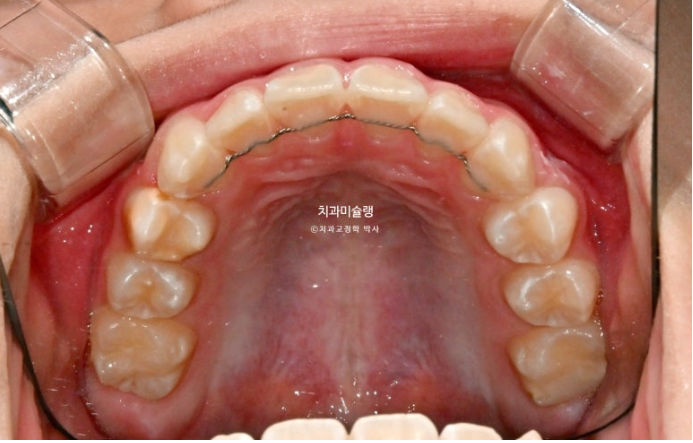

23.10

윗니가 아랫니를 많이 덮어 아래 앞니가 안 보이는 과개교합이 있습니다.

중심선 불일치도 보입니다.

윗니 뻗침이 있어서 돌출을 느끼는 상태입니다.

앞니 위아래 4개씩 총 8개 영구치 앞니는 약간의 삐뚤함이 있지만 큰 공간부족 없이 잘 나온 편 입니다.